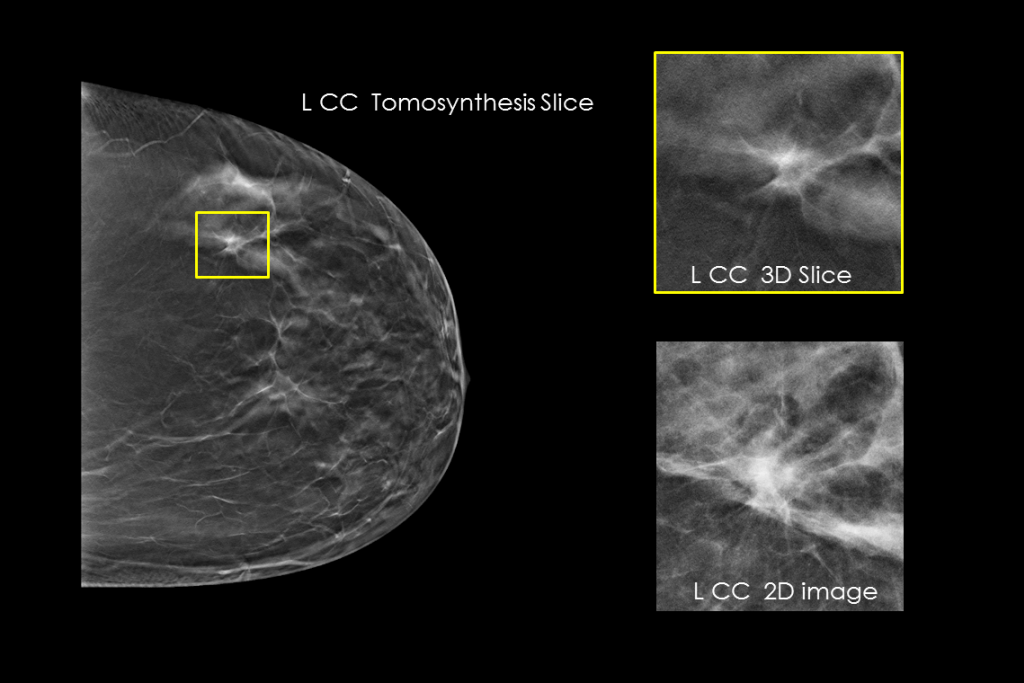

Clinical Images

Clinical images of breast scan mammography

Clinical images of breast scan with suspicious Lesion

Clinical images of breast scan